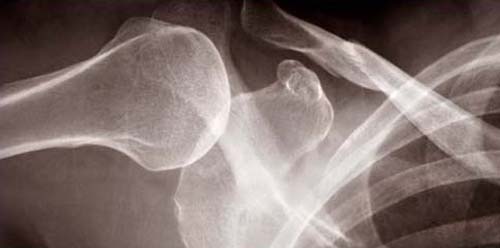

2003: As the body becomes fragile, what becomes of the self?

These images were shown in my MFA Thesis show at the Mass College of Art. In the first six images, I used the computer to combine my medical records with x-rays. The edges were created by encouraging the ink to run. The other four images are my x-rays that were modified in the computer and then printed large (2' x 4'). All images are inkjet prints on Vellum.